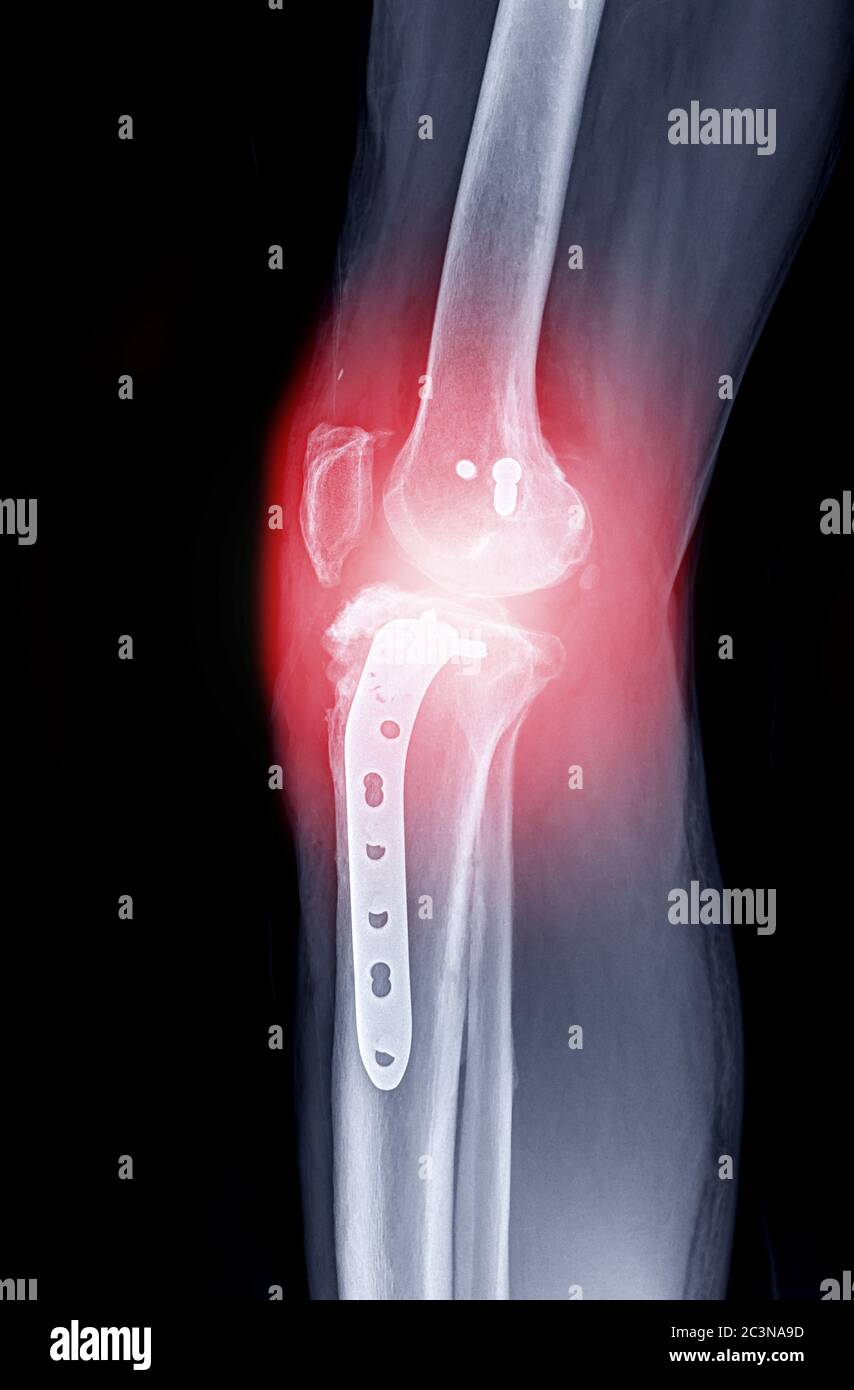

From depositphotos.com

Ray Knee Show Post Operation Right Knee Plate Screw Stock Photo by Knee Plates And Screws During the procedure, the bone fragments are repositioned into their. To do this, they will use tools like screws, metal plates, nails, wires, or pins. It’s also known as open. screws can be used for attachment of implants to bone, bone to bone fixation or for soft tissue fixation or anchorage. In conventional plates they act by. bone. Knee Plates And Screws.